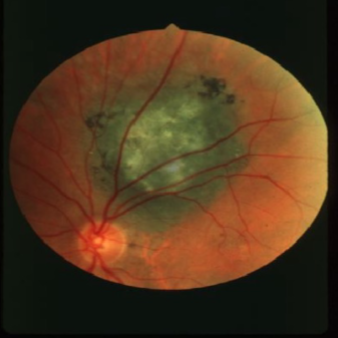

choroidal melanoma

melanoma

melanoma

melanoma

melanoma

melanoma

melanoma

melanoma

melanoma

melanoma

melanoma

melanoma

melanoma

melanoma

melanoma

melanoma

melanoma